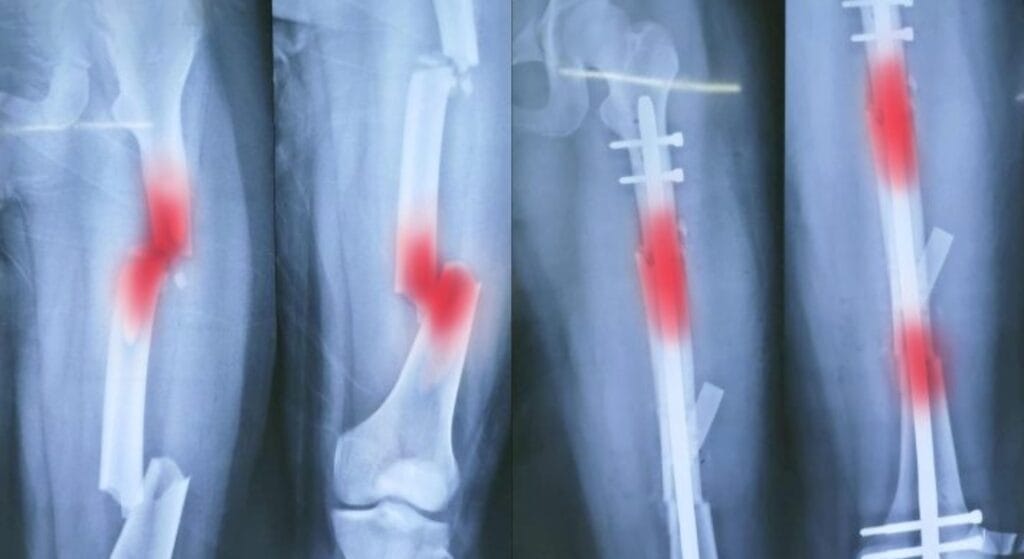

Gãy xương đùi

Xương đùi là xương dài và khỏe nhất trong cơ thể, nhưng khi gãy lại rất nguy hiểm vì khoang đùi có thể chứa lượng máu mất lên đến 1,5 lít. Đây là câu trả lời phổ biến khi hỏi gãy xương nào nguy hiểm nhất ở chi dưới.

Dấu hiệu: chân biến dạng rõ rệt, ngắn hơn bên còn lại, đau dữ dội, không thể nâng hoặc xoay chân.

Sơ cứu: bất động bằng nẹp dài từ hông tới gót, tránh di chuyển nhiều, gọi cấp cứu ngay.